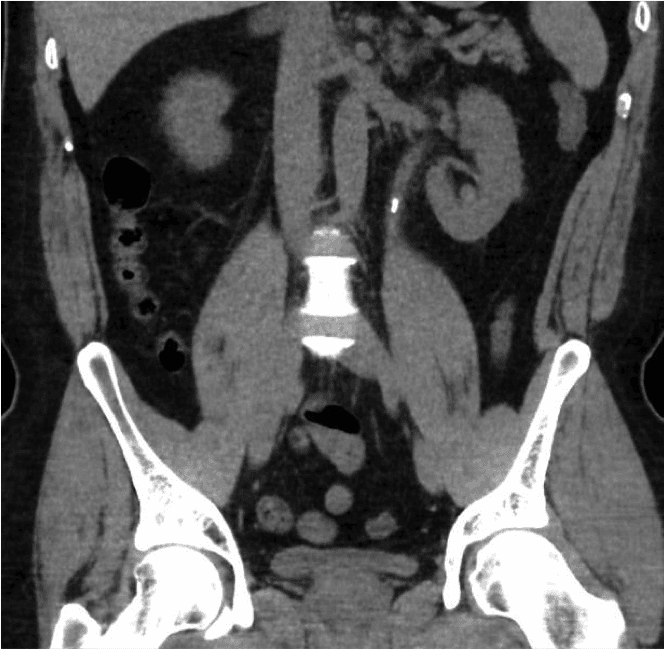

Dans un premier temps, une bandelette urinaire sera réalisée pour vérifier la présence de sang dans les urines et exclure une infection urinaire. Des analyses sanguines seront réalisées pour évaluer la fonction rénale et la calcification. L'examen diagnostique définitif pour les calculs est un scanner abdominal simple (TDM rein-uretère-vessie ou TDM KUB). Ce scanner permettra de déterminer la taille et la localisation des calculs, ce qui facilitera la planification du traitement.